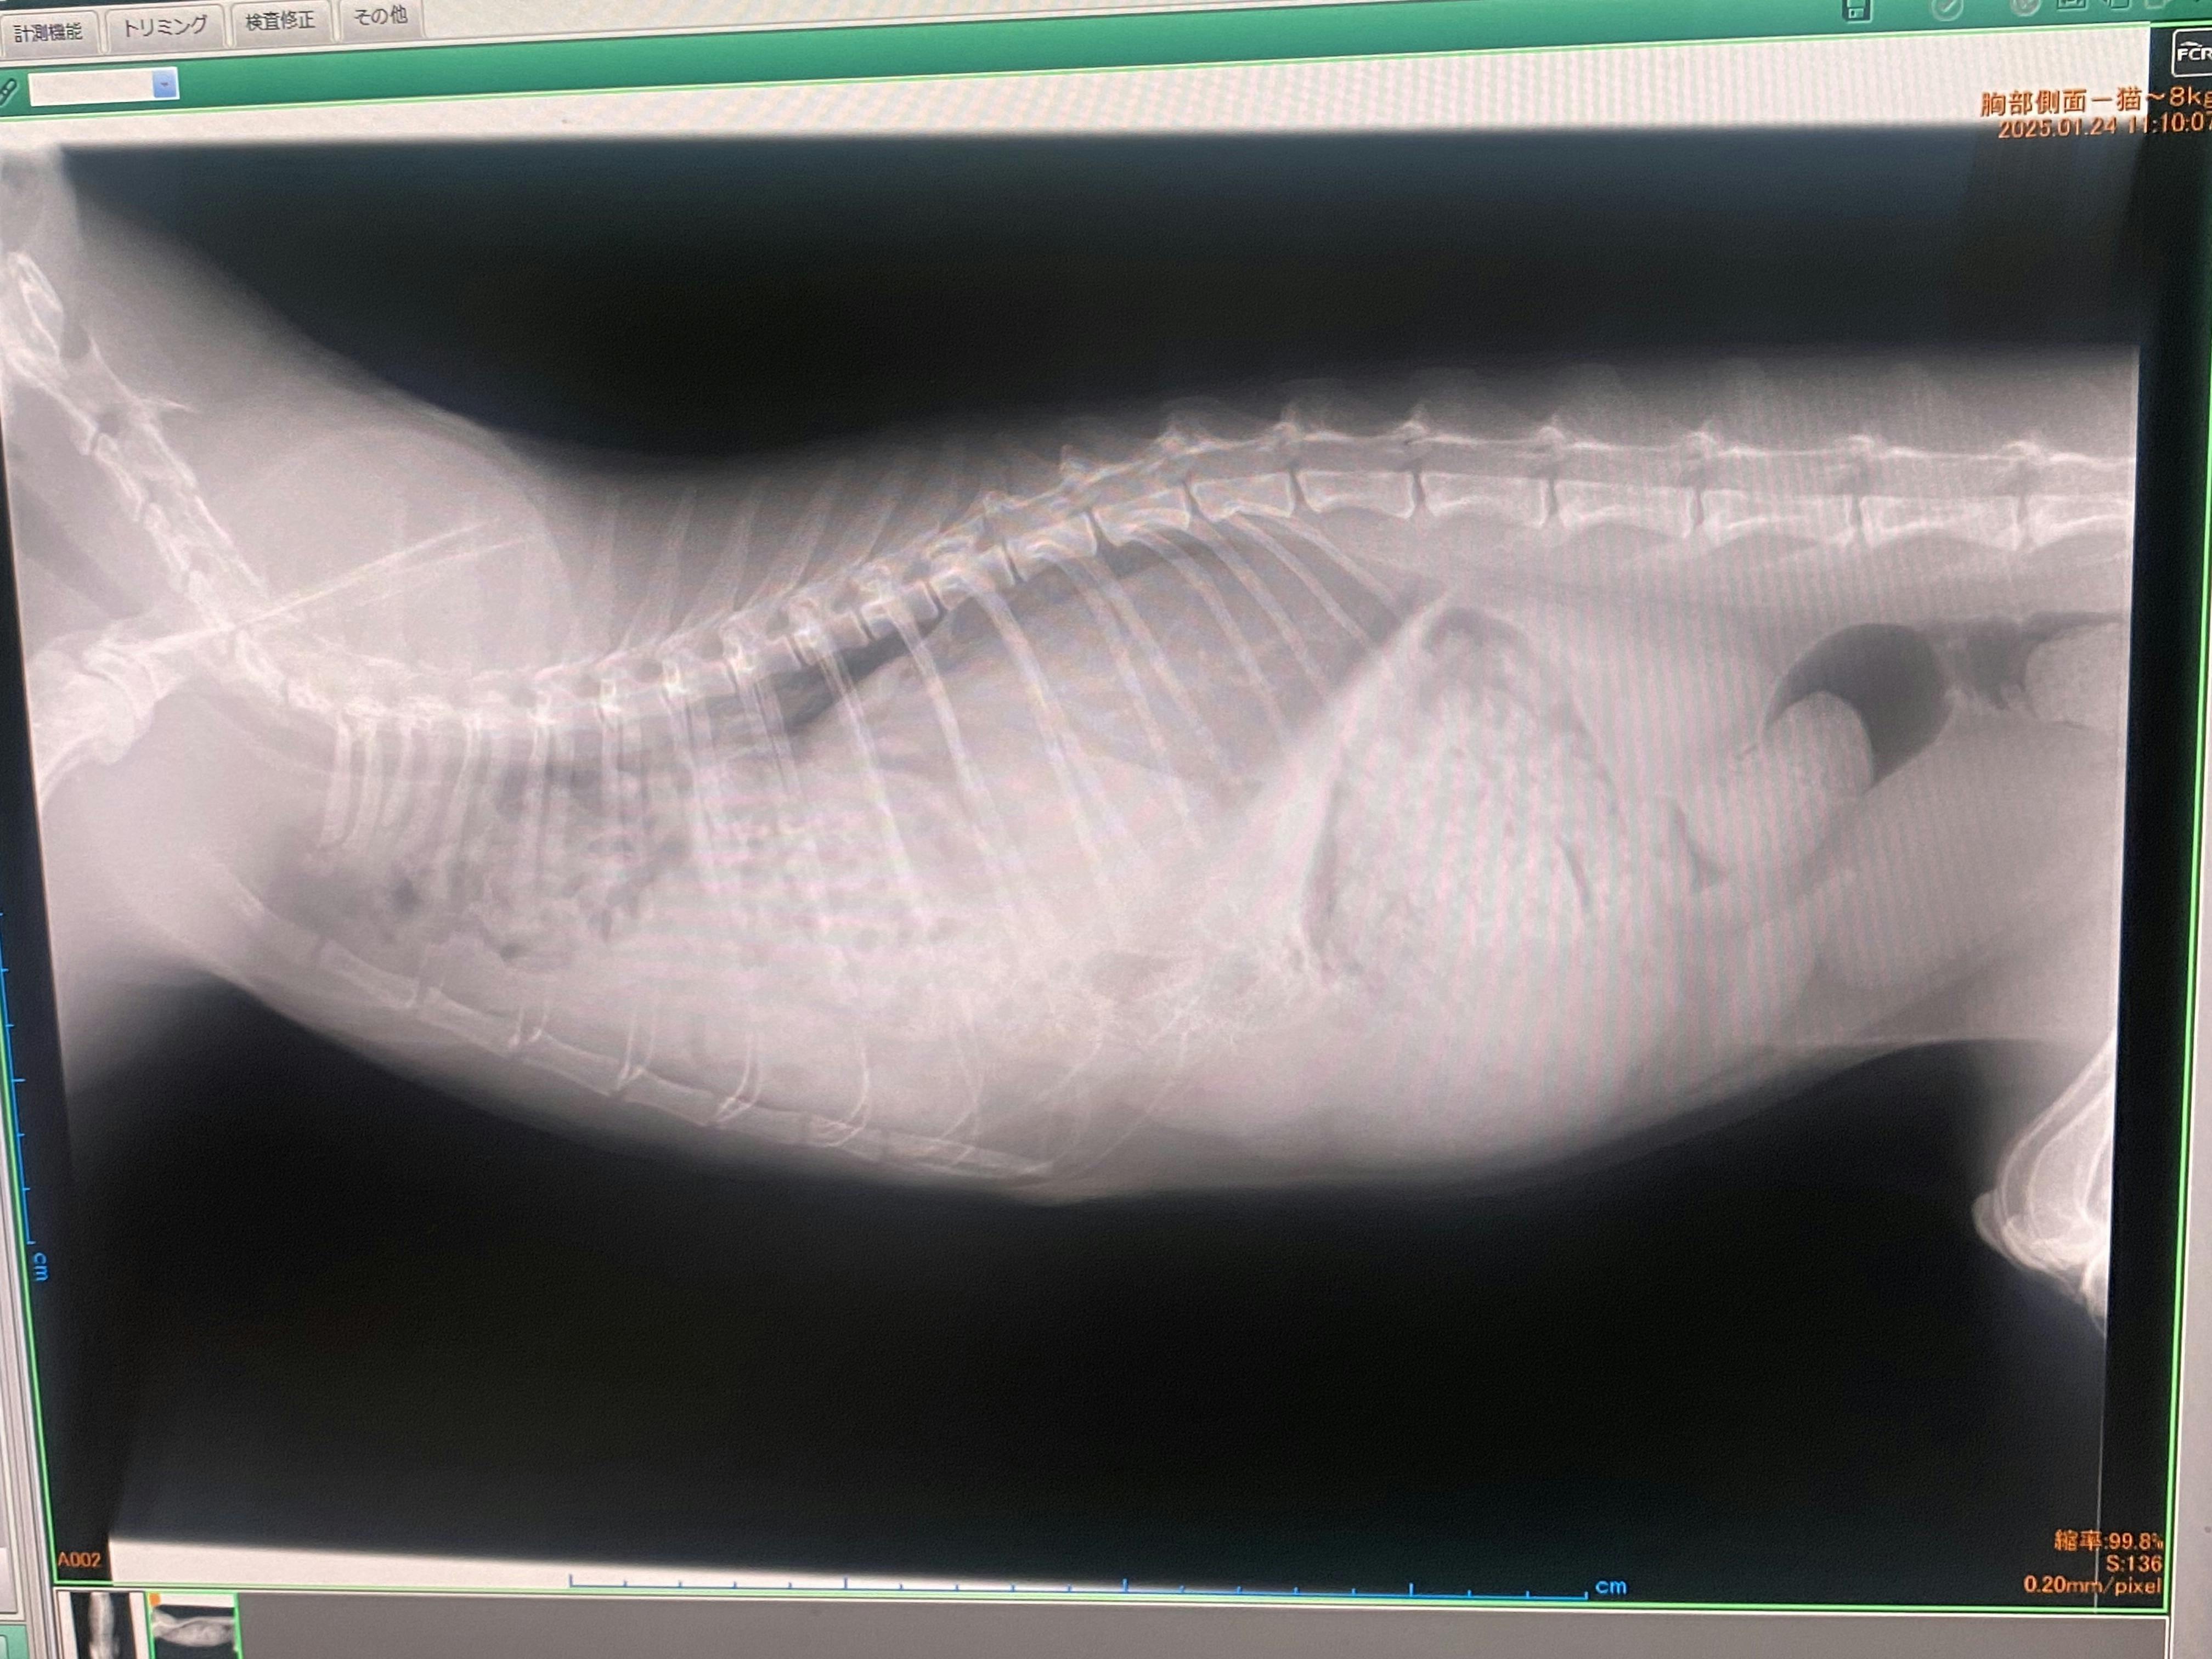

横隔膜ヘルニアは臓器を包む横隔膜が破れ、そこから臓器が出てしまう病気で野良猫に多いそうです。

交通事故などの強い衝撃で横隔膜が破れるとレントゲンのような状態になります。